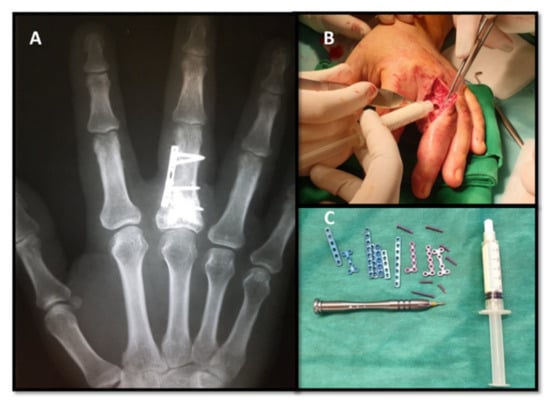

In this study, the recurrence rate was 6.6%, 1 of the 15 cases (Figure 4).

Range of motion (ROM) was measured by digital goniometer in the metacarpophalangeal (MCP), proximal interphalangeal (PIP) and distal interphalangeal (DIP) joints and then compared with the other hand. According to the Evaluation System of the American Society for Surgery of the Hand, 93% of the patients included in the present study attained “excellent” TAM (total active motion) at a 6-month follow-up (Table 1). The exception was the patient with recurrent enchondroma, who had a 20-degree flexion deficit in the MF joint (middle finger joint) and of 10 degrees in the PIP joint, which required tenolysis of the extensor apparatus, refused by the patient due to functional adaptation (Figure 5).

The treatment of choice for enchondroma is tumor curettage. The autologous bone graft used to consolidate bone defects is still considered the gold standard because it is the only biological material that possesses osteoinductive, osteogenetic and osteoconductive properties, fully integrated and transformed into trabecular bone [7,22]. However, a large number of complications are reported at the bone graft donor site, especially in the iliac crest. Complications include persistent postoperative pain, damage to the lateral femoral cutaneous nerve or ilioinguinal nerve, development of a hematoma or infection [23]. Autologous bone graft requires a longer operating time, sometimes a more laborious type of anesthesia and higher costs [24,25]. The postoperative recovery protocol depends on the strength of the remaining bone and the stability of the bone fixation mechanism. That is the reason why in some cases, fixation was performed with low-profile miniplates, which allow early motion from 5th day postoperatively [13]. In seven of our study cases, because of the large bone defect affecting over ½ of the cortical circumference, it was decided to use miniplates for osteosynthesis that allowed the early active and passive motion. Analyzing the results of this study, we found that there are no differences between DASH and TAM score values in patients receiving autologous bone graft or bone substitute, but the bone graft group recorded higher postoperative pain according to the VAS score, longer operative time and significantly higher costs. An additional advantage of using injectable bone substitutes could be the immediate mechanical stability they provide [12,26]. Gaasbek et al. reported good results following the use of calcium phosphate bone substitutes in 19 patients with enchondroma of the hand, as the material resorbed, on average, in 10 weeks and was progressively replaced by trabecular bone [27]. Yusuda reported good functional results after using calcium phosphate in the treatment of a series of patients with enchondroma of the hand or foot [28]. A possible disadvantage of synthetic bone substitutes could be its delayed integration, insufficient defect consolidation or immune rejection, complications not encountered in this study [29]. In the cases studied by us, we observed that in Takigawa type B enchondromas, we did not need bone grafting or bone substitutes to obtain good results. This could be due to smaller dimensions of the tumor with unicortical affecting. The type A and D enchondromas from our study benefitted from curettage and filling of bone defect with autologous bone graft or injectable bone substitute with similar results.

Recurrences are rare but can occur even 16 years after surgery [30]. The recurrence rate reported by some studies ranges from 7% to 14.3%. Because enchondromas are slow-growing benign tumors, recurrences can remain asymptomatic for a long time. Nevertheless, the use of bone cement can help in the early radiological observation of a lytic bone tumor. Because cement forms a highly radiopaque mass, the recurrence can be easily identified at the cement–bone interface [31]. Long-term follow-up is recommended to determine accurate recurrence rates [30,32]. Despite our small sample size (15 patients) and the potential for performance bias, a recurrence (6.6%) was detected on the 1-year follow-up X-ray (Figure 3).

Figure 4. Enchondroma recurrence at 1-year post curettage and autologous bone graft.